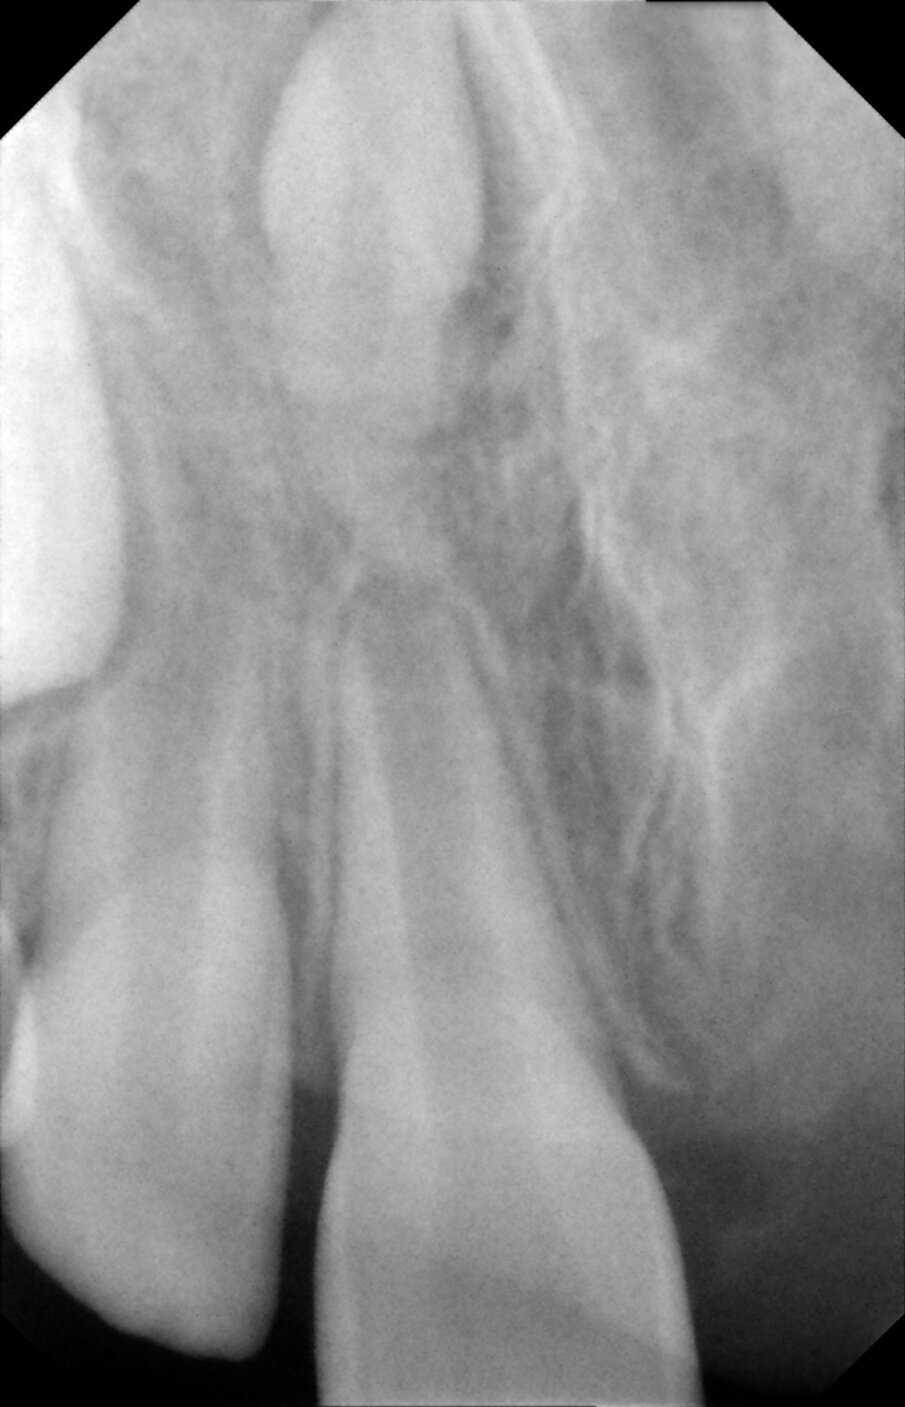

Periapical views of the upper maxillary incisors were obtained to rule out any root fractures (See Figures 4 a & b) revealed immature roots of teeth # 12, 11, 22, no root fractures and an inverted supernumerary apical to 11 and an empty socket of 21. There was no need for soft tissue radiographs as no tooth fragments were missing and the tooth was accounted for.

Figures 4a. Empty socket of 21 due to its avulsion. Notice the immature apices of 12, 11 and 22. In addition there was a supernumerary tooth/mesiodens

Figures 4b. Empy socket of 21 due to its avulsion. Notice the immature apices of 12, 11 and 22. In addition there was a supernumerary tooth/mesiodens